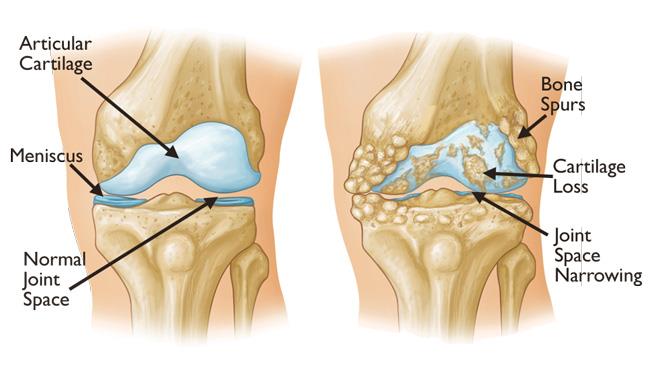

Giải phẫu – sinh lý bệnh

- Thoái hóa khớp gối là do các yếu tố cơ học và vô căn. Mặc dù thoái hóa khớp hiện nay được cho là một tình trạng phức tạp liên quan đến toàn bộ khớp, nhưng dấu hiệu đặc trưng của thoái hóa khớp là sự thay đổi sự cân bằng giữa quá trình thoái giáng và tổng hợp của sụn khớp và xương dưới sụn.

- Thoái hoá khớp có thể liên quan đến bất kỳ hoặc tất cả ba khoang đầu gối chính: khoang trong, khoang ngoài và bánh chè – đùi. Khoang trong thường bị ảnh hưởng nhiều nhất, dẫn đến hẹp khe khớp trong và do đó dẫn đến biến dạng khớp gối vẹo trong (genu varum). Thoái hoá khớp ở khoang ngoài có thể dẫn đến biến dạng khớp gối vẹo ngoài (genu valgum). Thoái hoá khớp trong một khoang cuối cùng có thể dẫn đến thoái hoá một khoang khác do các thay đổi sinh cơ học.

- Thoái hoá khớp ảnh hưởng đến tất cả các cấu trúc bên trong và xung quanh khớp. Có sự mất sụn hyaline của khớp. Quá trình tu sửa xương xảy ra, cùng với sự kéo căng của bao khớp và sự yếu đi của các cơ quanh khớp. Trong một số trường hợp, có thể xuất hiện tình trạng viêm bao hoạt dịch, lỏng lẻo dây chằng hoặc các tổn thương trong tủy xương.

- Thoái hoá khớp thường ảnh hưởng đến khớp theo cách không đồng dạng và khu trú. Các vùng mất sụn khu trú có thể làm tăng lực ép cục bộ lên khớp, dẫn đến mất sụn nhiều hơn. Với một diện tích sụn bị mất đủ lớn hoặc do quá trình tái tạo xương, khớp bị nghiêng và hình thành lệch trục.